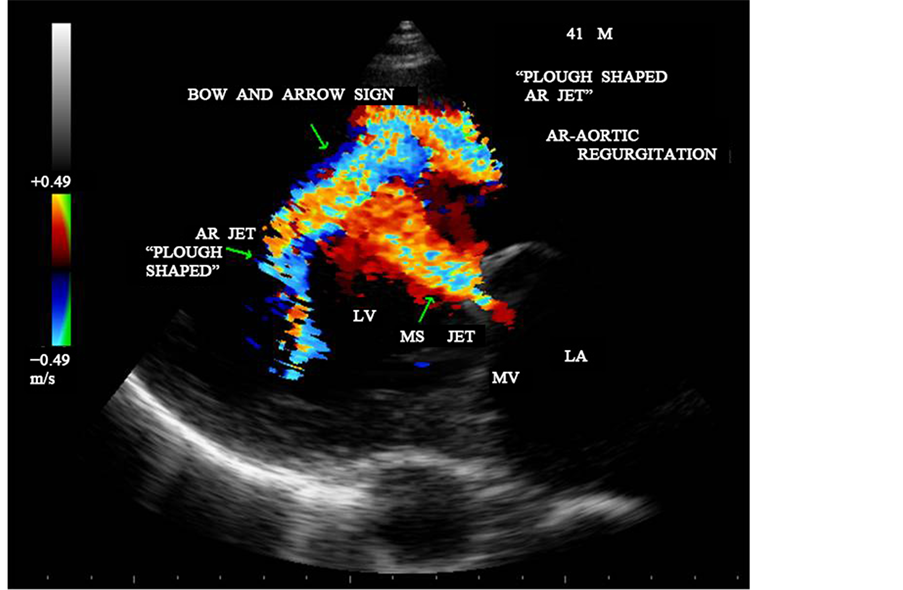

Figure 27. CW doppler showing the MS jet collide with AR jet and a “bow and arrow” appearance in parasternal long axis view.

Figure 28. CW doppler showing the MS and AR jets-“bow and arrow sign” in parasternal long axis view―“plough” shaped AR jet.

In general, rheumatic mitral stenosis results in a central stenotic orifice with flow directed from the center of the left atrium towards the apex of the left ventricle and collide with AR jet, producing a “bow and arrow” appearance as shown in Figure 27 and Figure 28. The differential features of etiological aspects of mitral stenosis (MS) are shown in Table 1.